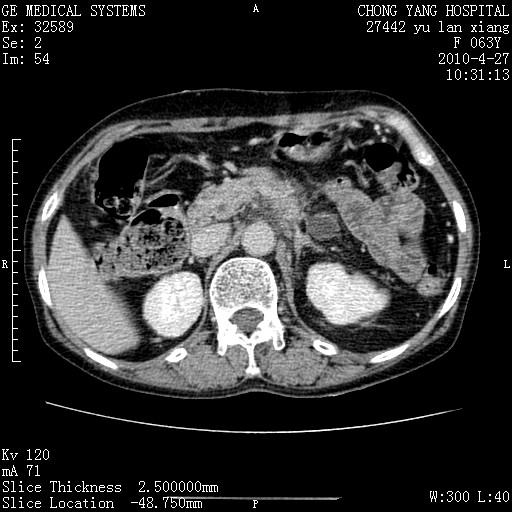

标题: CT26066:F63Y 上腹正中压痛半月,CA199:7400u/ml,MR示胰腺炎伴 [打印本页]

标题: CT26066:F63Y 上腹正中压痛半月,CA199:7400u/ml,MR示胰腺炎伴

胰腺癌侵犯腹腔动脉干-分支、胃壁、左侧膈肌伴胰周及腹膜后淋巴结转移、胆囊切除术后。

胰腺癌侵犯腹腔动脉干-分支、胃壁、左侧膈肌伴胰周及腹膜后淋巴结转移、胆囊未显影。